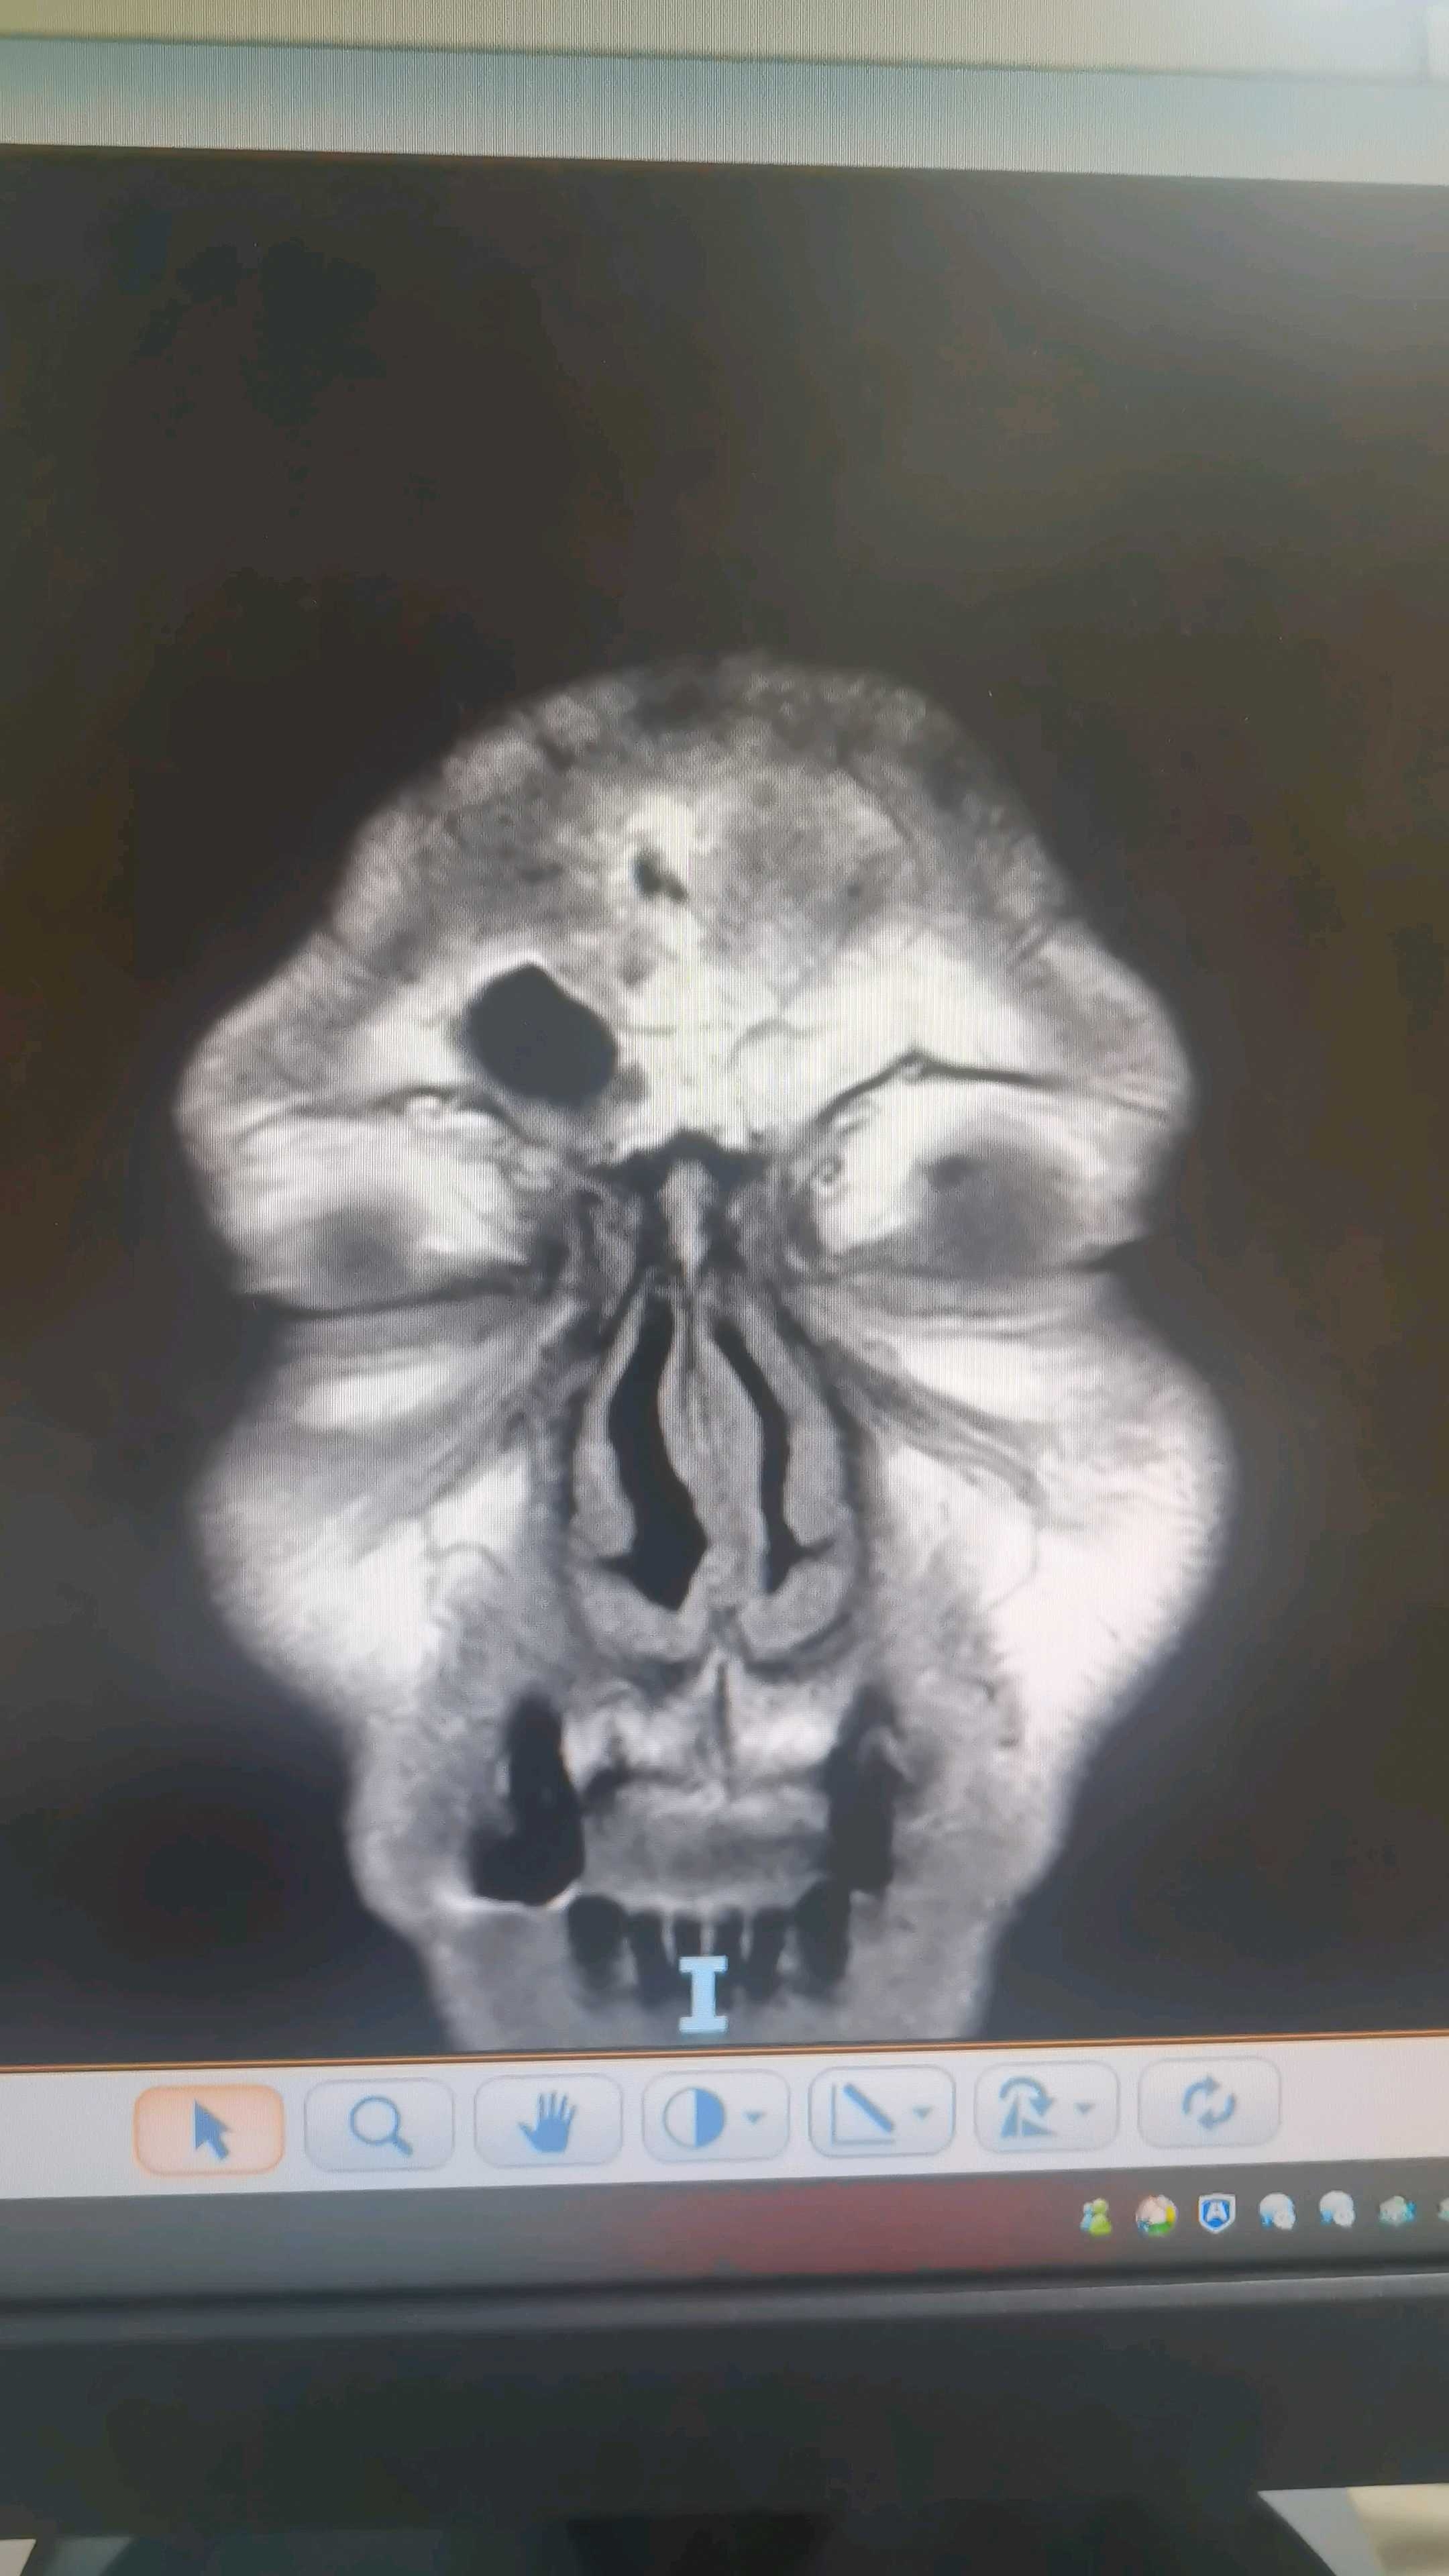

眼框mr